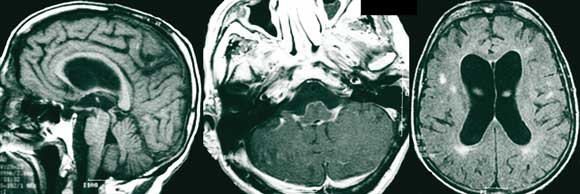

Magnetic resonance imaging (MRI) scans of the brain showed ventricular enlargement, supratentorial white-matter hyperintensities, and extensive leptomeningeal enhancement in the posterior fossa, brain stem and basal cisterns, with extension along the cranial nerves (Figure 1). The MRI results were reported as consistent with neurosarcoidosis. A SPECT (single-photon emission computed tomography) scan, undertaken to differentiate possible causes of dementia, demonstrated global hypoperfusion (Figure 2).

The differentiation of cryptococcosis from neurosarcoidosis in a patient with known sarcoidosis is difficult, as there is significant clinical overlap between the two disorders. CSF examination in both may show a raised cell count and protein level, and magnetic resonance imaging (as in our patient) may demonstrate non-specific leptomeningeal enhancement and hydrocephalus. In the setting of suspected neurosarcoidosis in patients with cognitive impairment and clinical or neuroradiological suggestion of meningeal involvement, the exclusion of cryptococcal disease through CSF analysis and culture is mandatory.